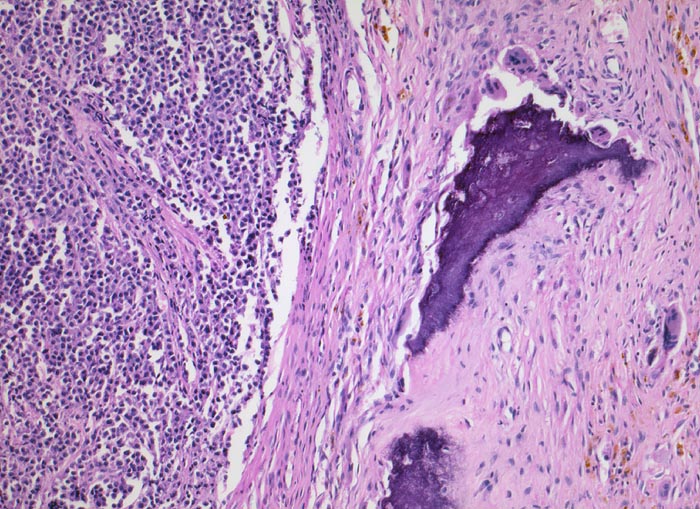

PathoPic – image database / PathoPic ID 4138 - Plasmazellmyelom

Plasmazellmyelom

Knochenmark, Wirbelkörper

Homogenes Tumorgewebe links im Bild ohne erkennbare Knochenmarksanteile. Ein Knochenbälkchen am Rande des Präparates wird von Osteoklasten resorbiert. Im Bindegewebe finden sich Makrophagen mit gelbbraunen Hämosiderineinlagerungen im Zytoplasma als Folge von Tumornekrosen und Blutungen.

Notfalleinweisung wegen umschriebenen Thoraxschmerzen ohne adäquates Trauma. Im Röntgenbild Nachweis multipler Frakturen der Wirbelsäule und der Rippen bei grobsträhniger Osteoporose. In der Serumelektrophorese Nachweis einer Paraproteinämie.